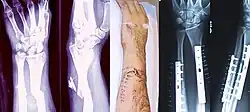

X-ray showing the proximal portion of a fractured tibia with an intramedullary nail

Proximal femur nail with locking and stabilisation screws for treatment of femur fractures of left thigh

When the initial post-fracture oedema or swelling goes down, the fracture may be placed in a removable brace or orthosis. If being treated with surgery, surgical nails, screws, plates, and wires are used to hold the fractured bone together more directly. Alternatively, fractured bones may be treated by the Ilizarov method, which is a form of an external fixator.